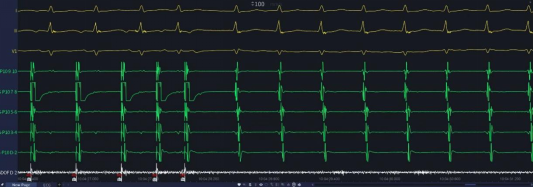

94岁的张奶奶因突发心悸、气短半天被紧急送入中山大学附属第三医院粤东医院。心电图检查提示为“阵发性室上性心动过速”,同时心功能指标BNP显著升高,诊断为“阵发性室上性心动过速、急性心力衰竭”。对于如此超高龄且脆弱的心脏,持续心动过速会急剧加重心衰,随时可能危及生命。而传统的药物治疗,在老年群体中往往因药效不佳或副作用大而受限。

手术当日,在多学科团队的严密护航下,心脏电生理团队精准定位病灶并成功实施“房室结慢径路改良术”。整个过程仅用时约一小时,生命体征平稳。